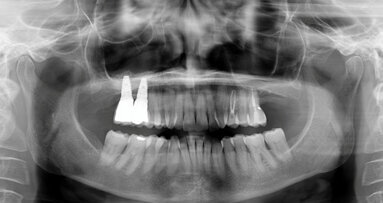

Case presentation: A 15-year-old male patient with a recurrent sinus tract involving the maxillary right incisors was referred for possible treatment with apical surgery. Root canal treatment and apical surgery had been undertaken unsuccessfully one year before. Radiographic examination revealed a radiolucent area surrounding the tooth apexes. A bone block was harvested from the apical area of the central incisor with ultrasound tips to gain access to the root end and apical surgery of both incisors was performed. The bone block graft was used to cover an apicomarginal bony defect of the maxillary lateral incisor. At the three-year follow-up, the teeth had no clinical signs or symptoms, and the periapical radiograph demonstrated complete healing around the apexes.

Conclusions: The use of a bone block graft to treat an apicomarginal defect in conjunction with apical surgery achieved complete healing of the periradicular tissue in this case.